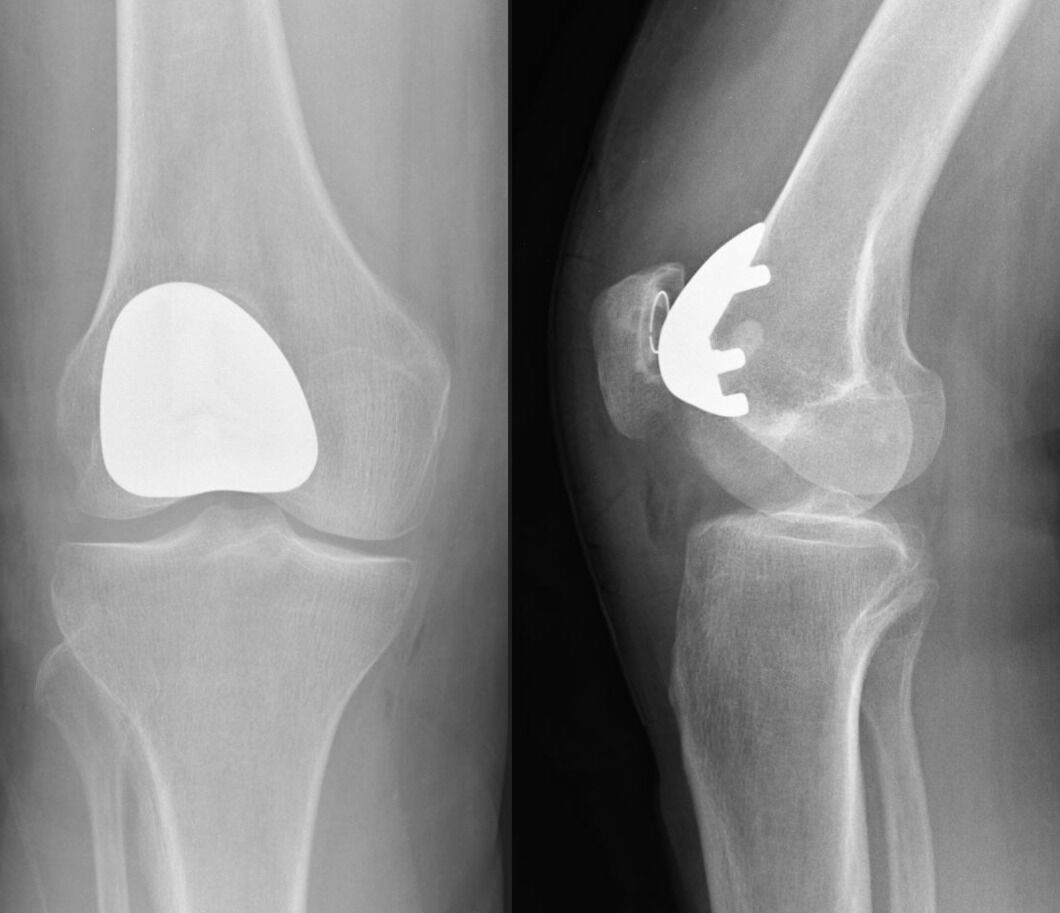

Patient's Guide to Total Knee Replacement ATX Orthopedics